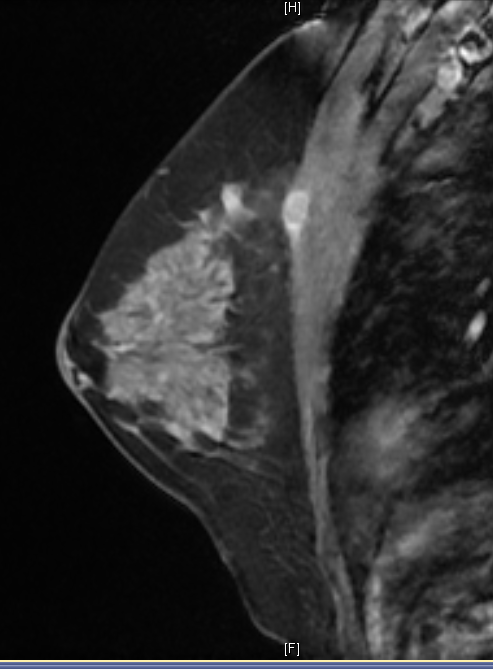

36 year old female comes with history of left breast lump. She is evaluated outside for same and HPR is papillary lesion. She comes to our hospital, we repeat her mammogram and USG, which is suggestive of a high density large mass with lobular margin in upper outer quadrant of left breast. As out side HPR is discordant with imaging finding, we repeat her biopsy and MRI. Repeat biopsy is suggestive of again papillary lesion. And MRI is suggestive of invasion of chest wall muscle. What do we do now?

Adenomyoepithelioma is a primary breast neoplasm of rare entity caused by proliferation of both epithelial and myoepithelial components, Benign to low grade malignant behavior and has a propensity for recurrence. Either epithelial or myoepithelial component can show malignant transformation so thorough evaluation recommended*. Overlap of histopathological features usually lead to misinterpretation as invasive carcinoma or intraductal papilloma or sclerosing adenosis. Complete wide excision with negative margins is standard treatment to prevent local recurrence. It is difficult to diagnose this on imaging alone, however familiarity with this rare entity to radiologist is essential to raise possibility.

Final histopathology was suggestive of Adenomyoepithelioma (AME). (Few foci of atypia were seen, however there was no malignancy)